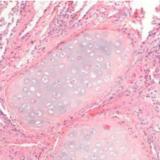

Data Challenge CardI-HACK : améliorer l’évaluation pronostique de la cardiomyopathie hypertrophique

Participez au Data Challenge CardI-HACK porté par l’IHU ICAN sur la cardiomyopathie hypertrophique.